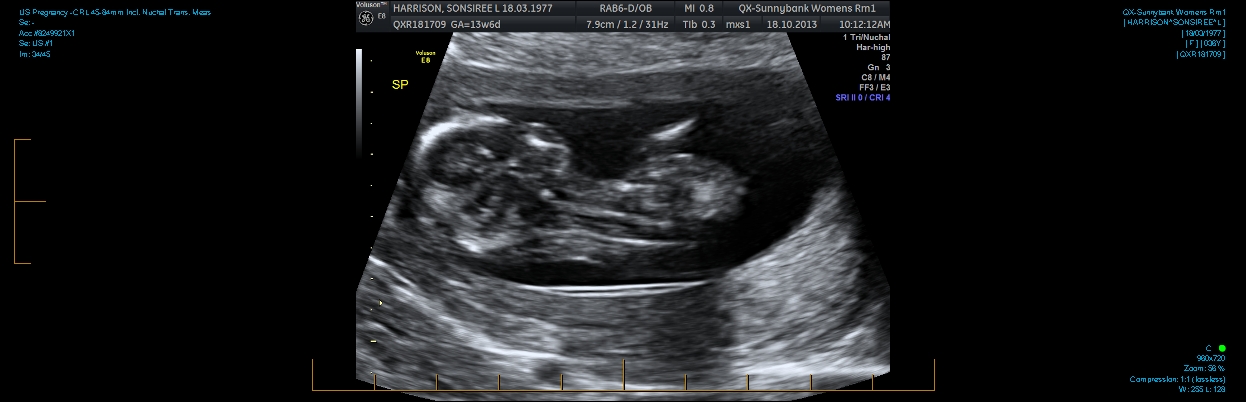

Hi everyone. I am 13w2d and can't figure out if there is a nub in these pics. I also have a potty shot. I know at this age they all have a little something. Can anyone tell me if it is prominent enough to say one way or the other?

Attachment 14828Attachment 14829Attachment 14831Attachment 14832Thanks in advance.